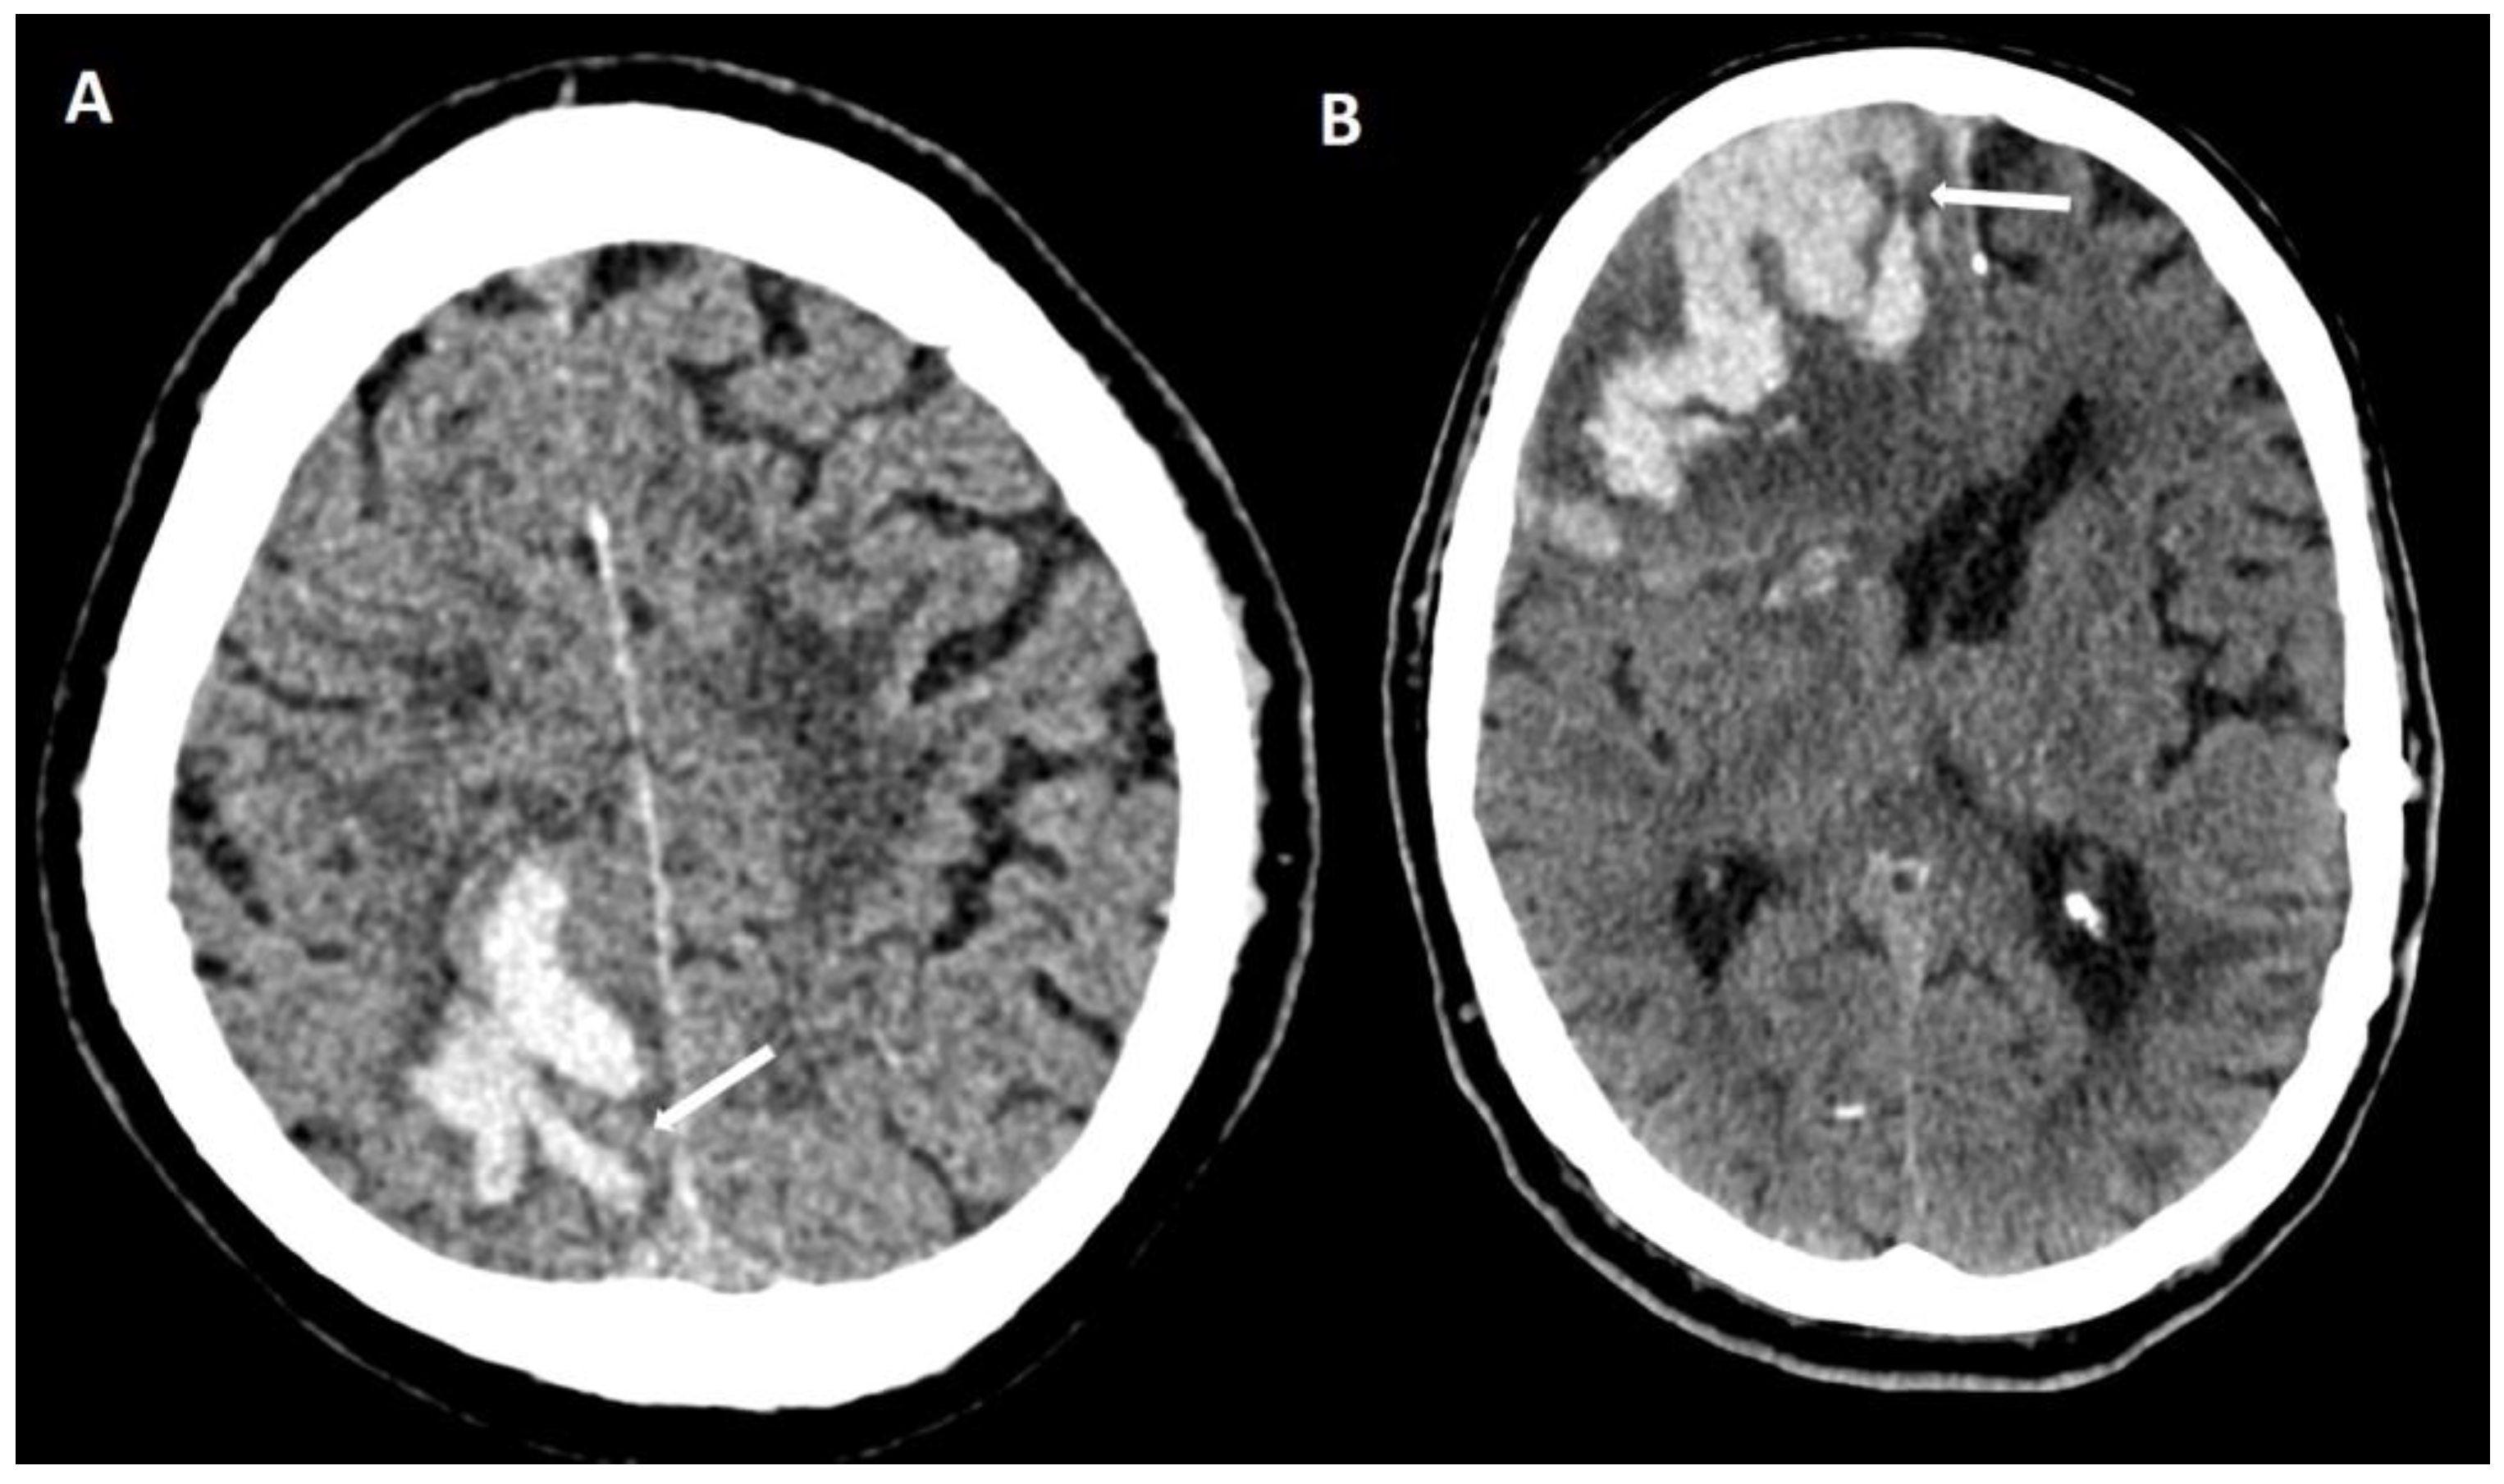

6.1. Finger-like Projections

6.2. Subarachnoid Extension of Lobar Hemorrhage

6.3. DWI Lesions

6.4. Lobar Lacunes